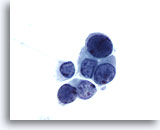

Urine prélevée à partir d’une vessie iléale, négatif

Les lavages d’urine prélevée à partir d’une vessie iléale contiennent des cellules glandulaires bénignes.

40x

Urine prélevée à partir d’une vessie iléale, négatif

Les lavages d’urine prélevée à partir d’une vessie iléale contiennent des cellules glandulaires bénignes.

40x